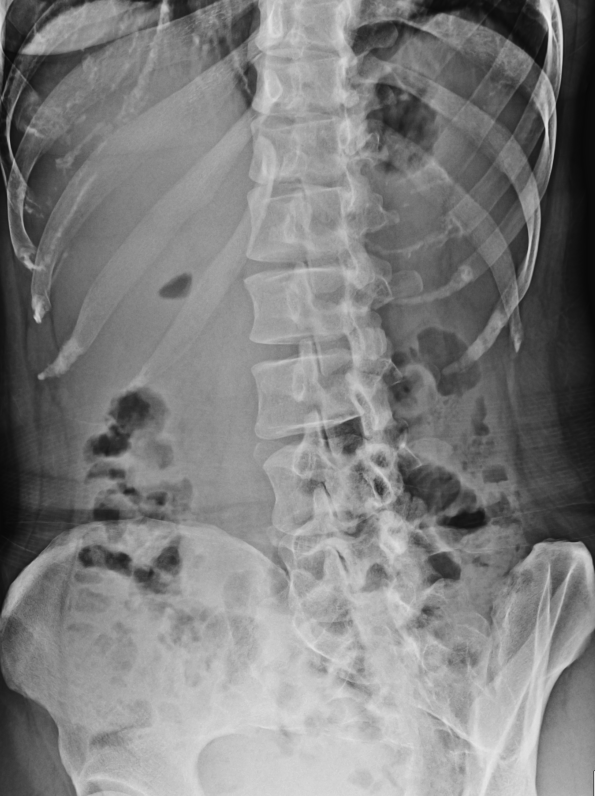

LAT 촬영

- 허리뼈의 구조적 이상이나 골절 등 전체적인 평가가 가장 용이.

- 골절 관찰 이상적

- 옆으로 누워 촬영시 상완을 가슴과 90도 각도, 전완부가 가슴과 수평이 되게 하는 자세로 촬영해야 팔로인한 가슴, 허리뼈 왜곡을 최소화할 수 있다. (팔베게 자세)

- 누워 촬영시 다리사이, 가슴부위 보조기구를 올려주면 각도 보상이 가능하나 일반적인 로컬에선 저런게 있을리 만무하니 패스.

- 등을 위에서 봤을때 바닥과 수직을 이루게 하는게 최선인듯.

강직성 척추염

- 허리뼈 및 주변 조직들이 딱딱하게 굳어 대나무같은 형상을 관찰 할 수 있다.